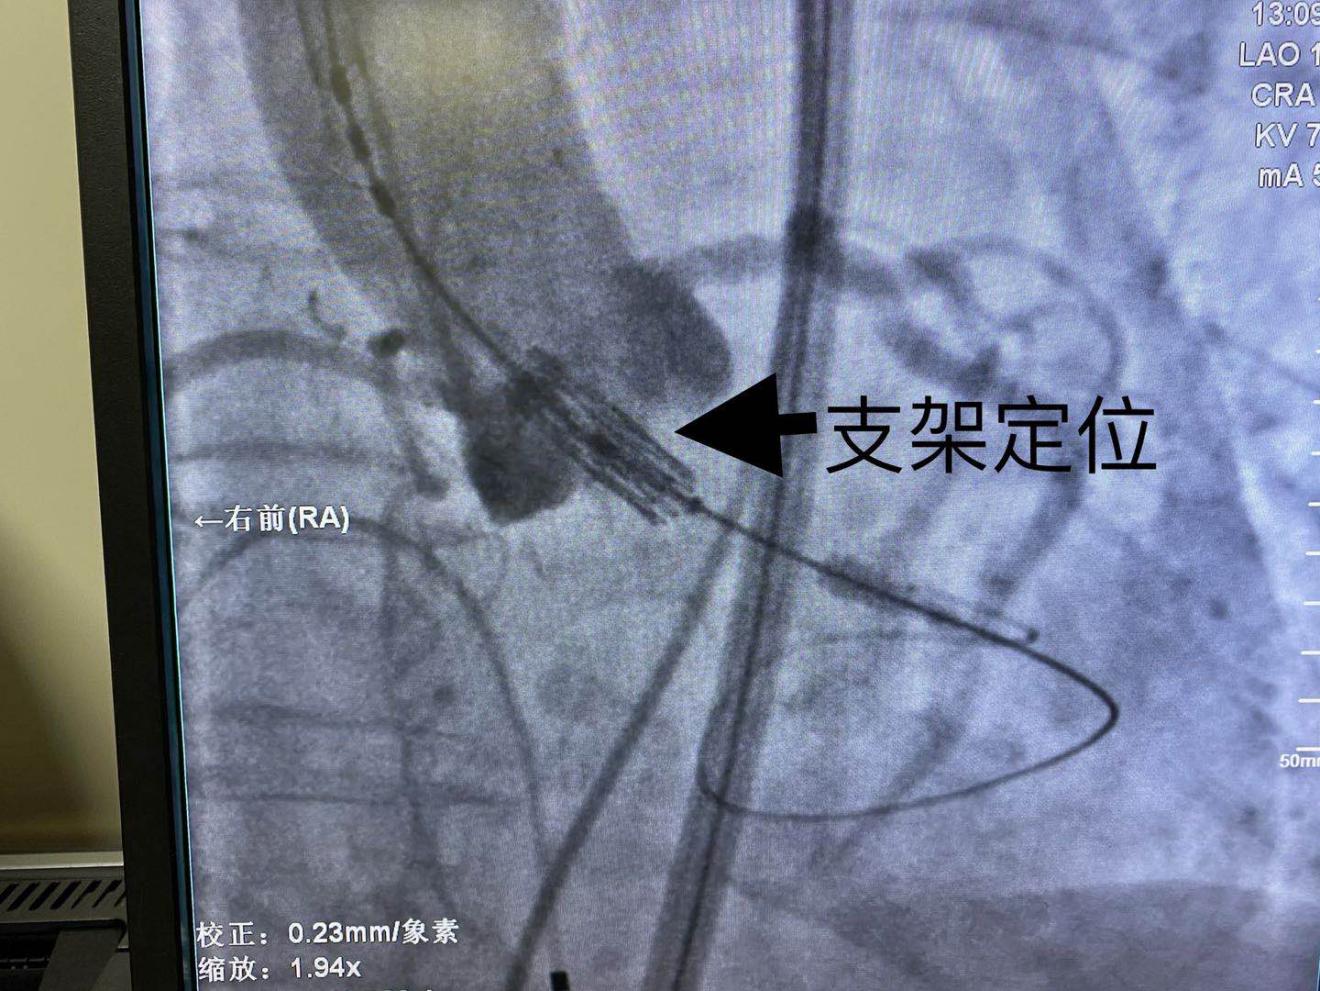

患者于杂交手术室,气管插管、静脉麻醉后,穿刺股动脉、股静脉,以右侧股动脉为主要入路,置入14F的股动脉鞘管,导丝跨瓣、球囊扩张,紧张有序而又有条不紊。根据术前CT评估,选择20mm的Edwards Sapien 3瓣膜。瓣膜支架准确定位—180次/分快速起搏—支架球囊扩张—成功释放瓣膜,术后即刻跨瓣压差接近0,无明显瓣周漏,顺利结束手术,整个手术过程用时约50分钟。

(SAPIEN 3瓣膜释放过程)